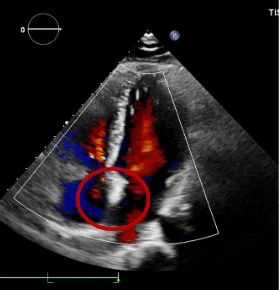

经食道心脏超声:四腔心切面缺口径宽约0.35cm,缺损边缘距二尖瓣环约2.1cm,距房顶约2.5cm,大动脉短轴切面缺口经宽0.36cm,主动脉后方无残边。双房切面缺口径约0.35cm,缺损边缘距上腔静脉约2.6cm,距下腔静脉约2.7cm。CDFI:房间隔连续中断处见左向右分流信号。

TEE可见房间隔中断出左向右分流

TEE测量缺损大小

肺动静脉CTA未见异常;经食道超声检查明确为小房缺,缺损直径约0.35cm。